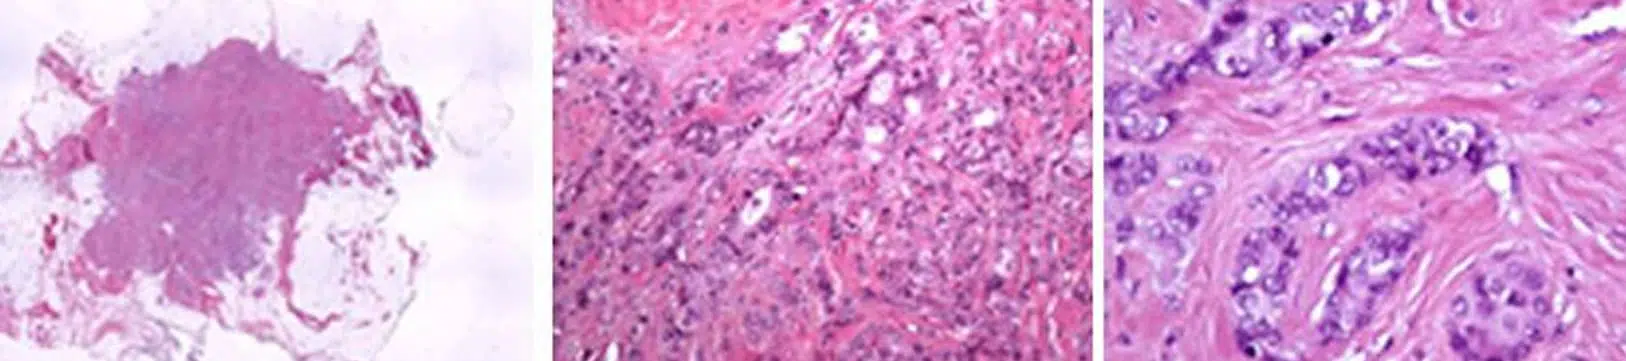

الفحص التشريحي المرضي

يُعد الفحص التشريحي المرضي للأنسجة المأخوذة تحت المجهر أمرًا أساسيًا.

يؤكد تشخيص سرطان الثدي ويحدد خصائص الورم. كما يُنشئ “بطاقة هوية” حقيقية للسرطان، وهو أمر ضروري لاختيار العلاجات المناسبة.

تحليل الخلايا السرطانية

استنادًا إلى مدى تشابه الخلايا السرطانية مع الخلايا الطبيعية في الثدي، يُحدد أخصائي التشريح المرضي ما إذا كان السرطان مُتمايزًا أو غير مُتمايز. كلما زاد تشابه الخلايا السرطانية مع الخلايا الطبيعية، زاد تمايزها، مما يعني أنها أقل عدوانية.

بناءً على هذا المعيار وملاحظات أخرى، يُحدد أخصائي التشريح المرضي درجة السرطان وفقًا لتصنيف Elston-Ellis histopronostic:

- الدرجة I: الورم قليل العدوانية

- الدرجة II: الورم متوسط العدوانية، وهو الأكثر شيوعًا

- الدرجة III: الورم عدواني

تحديد العلامات البيولوجية

يقوم أخصائي التشريح المرضي بتحليل العلامات البيولوجية (المؤشرات الحيوية) الموجودة على سطح الخلايا السرطانية. تساعد هذه الخصائص البيولوجية في تحديد نوع السرطان واختيار العلاج الأنسب للمريضة.